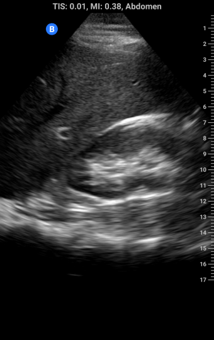

Depth: increasing depth brings far away structures onto the screen and simultaneously makes everything appear smaller; think of it like zooming out on digital map, you will seem more but with less detail. Decreasing depth does the opposite, we don’t seem as far down but there is greater detail. Optimal depth is achieved when all structures of interest are in the image field but as large as possible. Watch what happens as we increase depth in the images below (note increasing depth markers on the right of each image):

B-mode: Brightness mode, or B-mode, is the standard mode for ultrasound images and shows a 2D greyscale image.